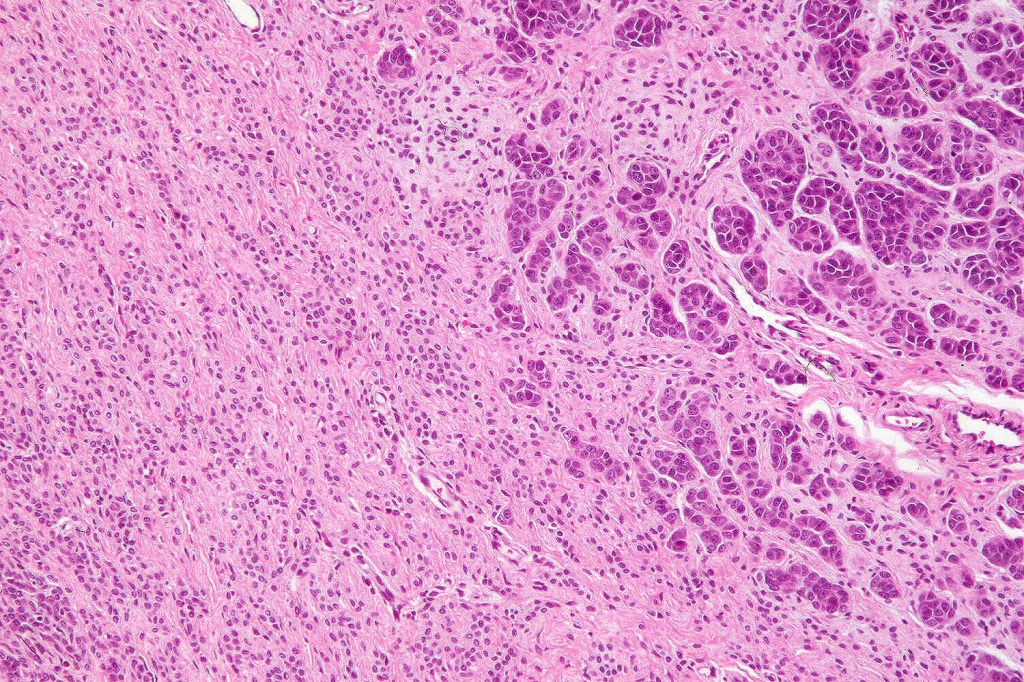

•The nodule generally merges with the adjacent nevus but sometimes it can be sharply circumscribed

•It is hypercellular and most often composed of epithelioid cells showing little pleomorphism & only occasional mitoses

•The constituent cells are generally larger than the adjacent nevus cells

•Some examples show more marked pleomorphism with prominent nucleoli and increased mitotic activity but abnormal mitoses are not a feature. These are not associated with any sinister biological potential

•Absence of necrosis, hemorrhage or Pagetoid spread in the overlying epidermis